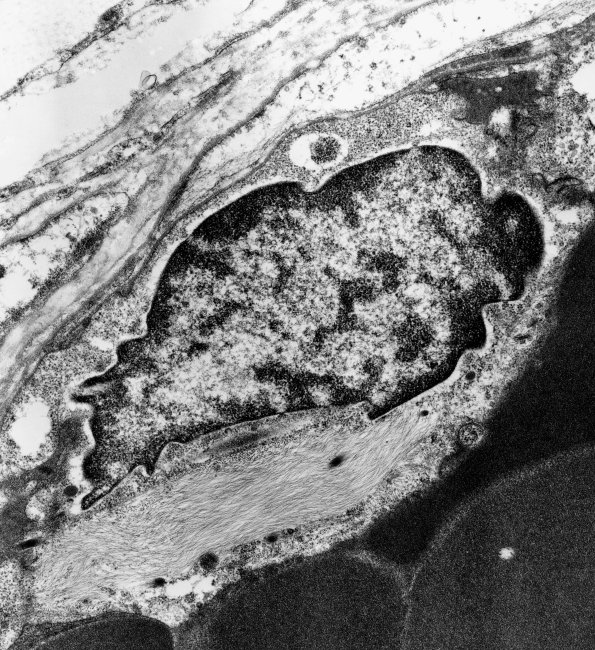

An endothelial cell with a collection of intermediate filaments. (electron micrograph)